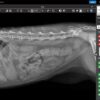

✔ Υψηλής Ευκρίνειας Ψηφιακή Ακτινογραφία

- Υποστήριξη για ψηφιακά αισθητήρια (DDR) & κλασικά ακτινογραφικά φιλμ.

- Σταθερή υψηλή τάση 60kV & 2mA για καθαρή εικόνα χωρίς θόρυβο.